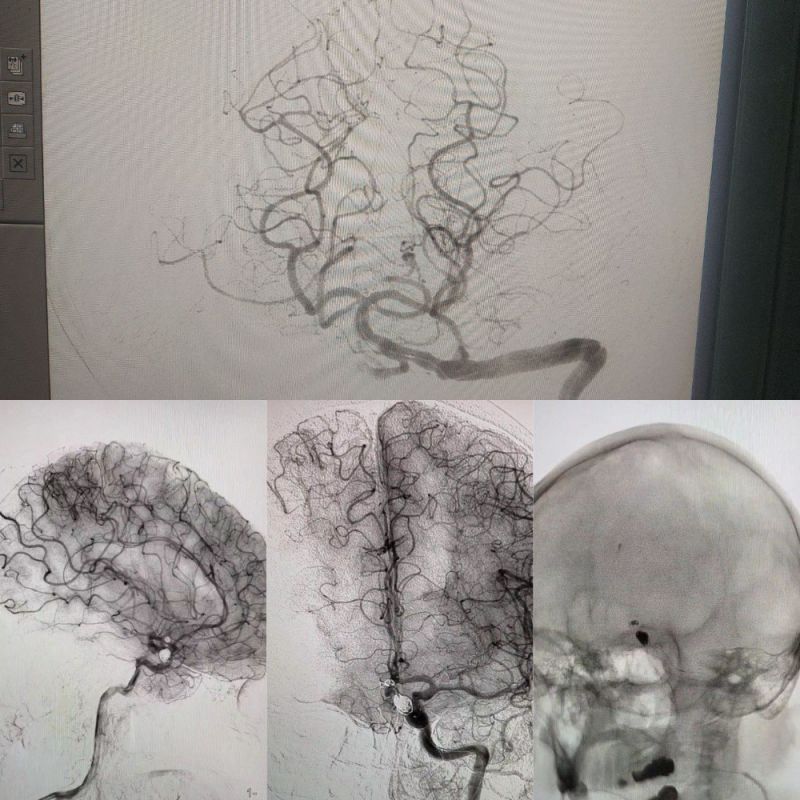

В ЛНР впервые с 2014 года провели две успешные операции по эмболизации аневризмы головного мозгаНа базе нейрохирургического отделения Луганской республиканской клинической больницы под...